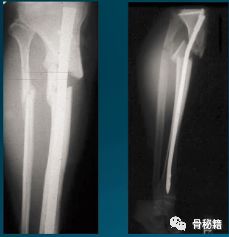

小钢板辅助复位,可以在胫骨棘前方行一个小切口,固定一个小钢板来辅助复位和维持复位,植入髓内钉后可取出也可不取。

该例骨折,移位较大,复位困难,可以先置放个小钢板